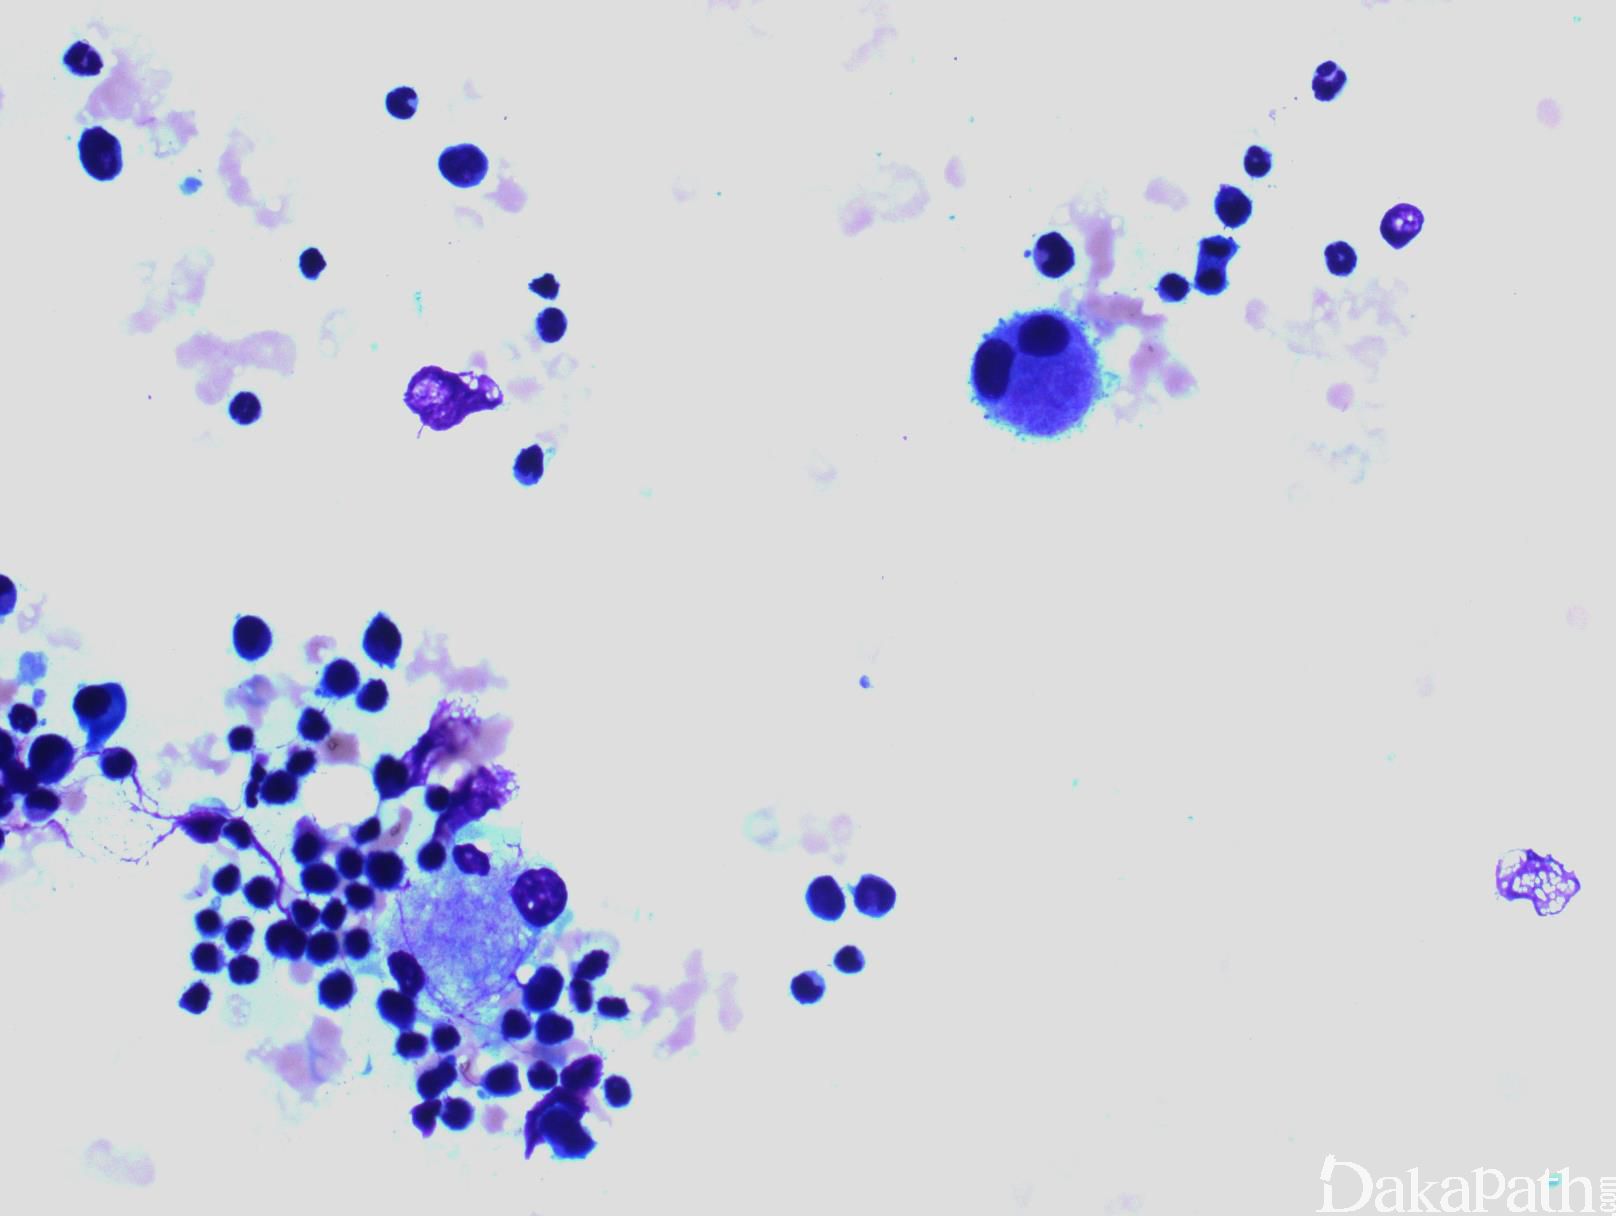

CMML 的标志性特征是外周血单核细胞增高。根据定义,外周血单核细胞计数总是 ≥1×109/L,通常 2-5×109/L,但可以高达 80×109/L,且单核细胞要占白细胞的 10%以上。CMML 外周血中单核细胞为的成熟型,无明显形态学异常;但可出现胞浆颗粒和核分叶异常及纤细的核染色质,具有这类特征细胞最好称为异常单核细胞,用于描述有一定形态学异常和轻微不成熟而又缺乏幼单核细胞特点的单核细胞。幼单核细胞在 CMML 中被认为等同于原始细胞,细胞较不成熟,核染色质细腻、核仁小而不明显,胞质含细颗粒。原始细胞包括原粒细胞和原单核细胞。原单核细胞体积大,胞质丰富,弱噬碱,可含有细颗粒,一个或多个突出核仁。原粒细胞、原单核细胞和幼单核细胞与更为成熟的异常单核细胞和正常单核细胞的区分,对于 CMML 和 AML 的鉴别诊断非常重要。如果原始细胞(原粒细胞、原单核细胞和幼单核细胞)占白细胞总数 20%或以上,则应诊断为 AML。中性粒细胞计数可以增高、正常或减低,前体粒细胞(早幼粒、中幼粒、晚幼粒)应<10%。粒细胞有不同程度的异形性(如少颗粒、低分叶)。可有轻度噬碱细胞增高,噬酸粒细胞一般正常或轻度增多,但偶而显著增高,此时可诊断为 CMML 伴噬酸细胞增高,但髓/淋系肿瘤伴噬酸细胞增高和特异遗传学异常(如 PDGFRB)必须除外。常有轻度贫血,血小板计数不等,可中度减少并形态异常。多数病例骨髓细胞密度增高,但也可以正常,减低罕见。最突出表现是粒系增殖,也总是有单核增生(程度不等),但骨髓涂片形态学不容易辨认。细胞化学或免疫组化染色有助识别单核及其前体细胞。如同外周血,粒系有不同呈度异形性,红系也有轻度异形性,80%病例有巨核细胞异形如微巨核细胞或少分叶巨核细胞。2017 年版 WHO 根据外周血和骨髓中原始细胞(原粒细胞、原单核细胞、幼单核细胞)比例,将 CMML 分为 3 种类型:CMML0,原始细胞外周血中 <2%和骨髓中 <5%,无 Auer 小体;CMML1,原始细胞外周血中 2-4% (< 5%),骨髓中 5-9% (<10%),无 Auer 小体;CMML2,原始细胞外周血中 5-19% (<20%),骨髓中 10-19% (<20%) ,或有 Auer 小体。

b 原始细胞和其等同细胞包括原始粒细胞、原始单核细胞和幼单核细胞。幼单核细胞系单核细胞前体,具有丰富的淡灰色或微噬碱胞质、散在细颗粒、精细分布点状染色质,等度不等的突出核仁和纤细的核折叠。外周血和骨髓中的异常单核细胞不能计作原始细胞。